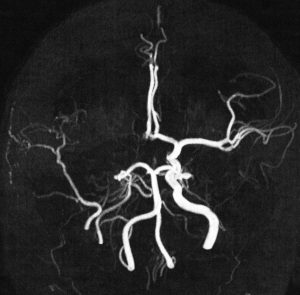

4歳の時に頭蓋咽頭腫に対して50グレイの分割照射を受けました。両側の内頸動脈と前交通動脈が被曝しています。16歳(12年後)に左片麻痺の虚血発作を生じました。右内頸動脈が閉塞してウィルス動脈輪閉塞(モヤモヤ病)になっていました。前交通動脈に動脈瘤(赤矢印)もできていました。小児の頭蓋咽頭腫への放射線治療ではかなり高率に閉塞性脳血管障害を生じるのですが,治療後10年以上がたってから起るので,治療を行った医師はそれをみることはほとんどありません。

小児のクラニオ:放射線治療後の脳梗塞

3歳の時に鞍上部クラニオに40グレイの放射線治療を受けました。31歳(28年後)で右前頭葉に脳梗塞を生じました。右内頸動脈と左前大脳動脈が閉塞したウィルス動脈輪閉塞症(モヤモヤ病)になっています。右の中硬膜動脈から右大脳に血流が入っています。

5歳でガンマナイフ,8歳と10歳の時にサイバーナイフ治療を受けました。右内頸動脈が閉塞してウィルス動脈輪閉塞(モヤモヤ病)になりました。この画像は10歳時のものです。右中硬膜動脈から右の前頭葉と側頭葉に血流が入っていてモヤモヤ病の病態です。脳虚血発作や脳梗塞はない無症候性のものです。